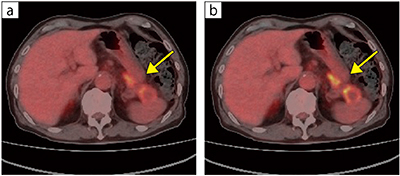

図2 膵尾部がん(検診にて指摘)

a:Conventional(CaLM)

b:AiCE-i

PET-CT検診にて膵尾部がんを指摘した例。AiCE-iを用いた画像の方が腫瘍の境界がより明らかである。

「AiCE-iでは、CaLMと比べノイズが低減された明瞭な画像を得られます。頭部では皮髄境界が非常に明瞭になりますし、腫瘍も辺縁が明瞭化し浸潤範囲を想定しやすくなります。また、肝臓などの結節においてもCaLMよりもAiCE-iの方がより高いコントラストで観察できます。両画像の特性については、引き続き症例を重ねて比較検討していきます」